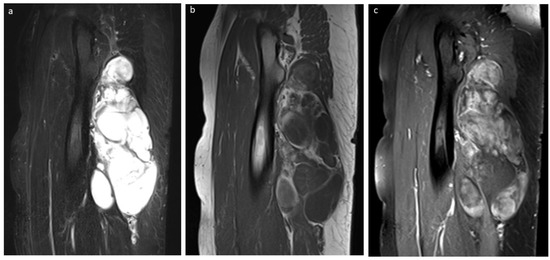

3.5. Liposarcoma